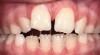

A common developmental abnormality is a localized anterior crossbite on permanent incisors, which may lead to trauma to these teeth. The most common cause of localized incisor crossbite is an anterior occlusal interference, which causes a functional shift when the patient moves from centric relation to centric occlusion (Figure 1 and Figure 2). This is not a true class III malocclusion, and proper diagnosis is critical to select the correct treatment. Sometimes this bite relationship is called a pseudo-class III relationship.2 Intervention in these cases is important because these teeth are at higher risk for recession, periodontal damage, and incisal chipping. Limited anterior braces and sometimes a palatal expander may be used to place the maxillary incisors facial to the mandibular incisors; this is referred to as "jumping the bite."

Fig 1. Functional shift in centric occlusion.

Figure 1

Fig 2. Functional shift in centric relation.

Figure 2